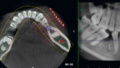

レントゲン撮影、口腔内写真、歯のスキャンを行い、治療プランを設計。 - クリンチェック(シミュレーション)